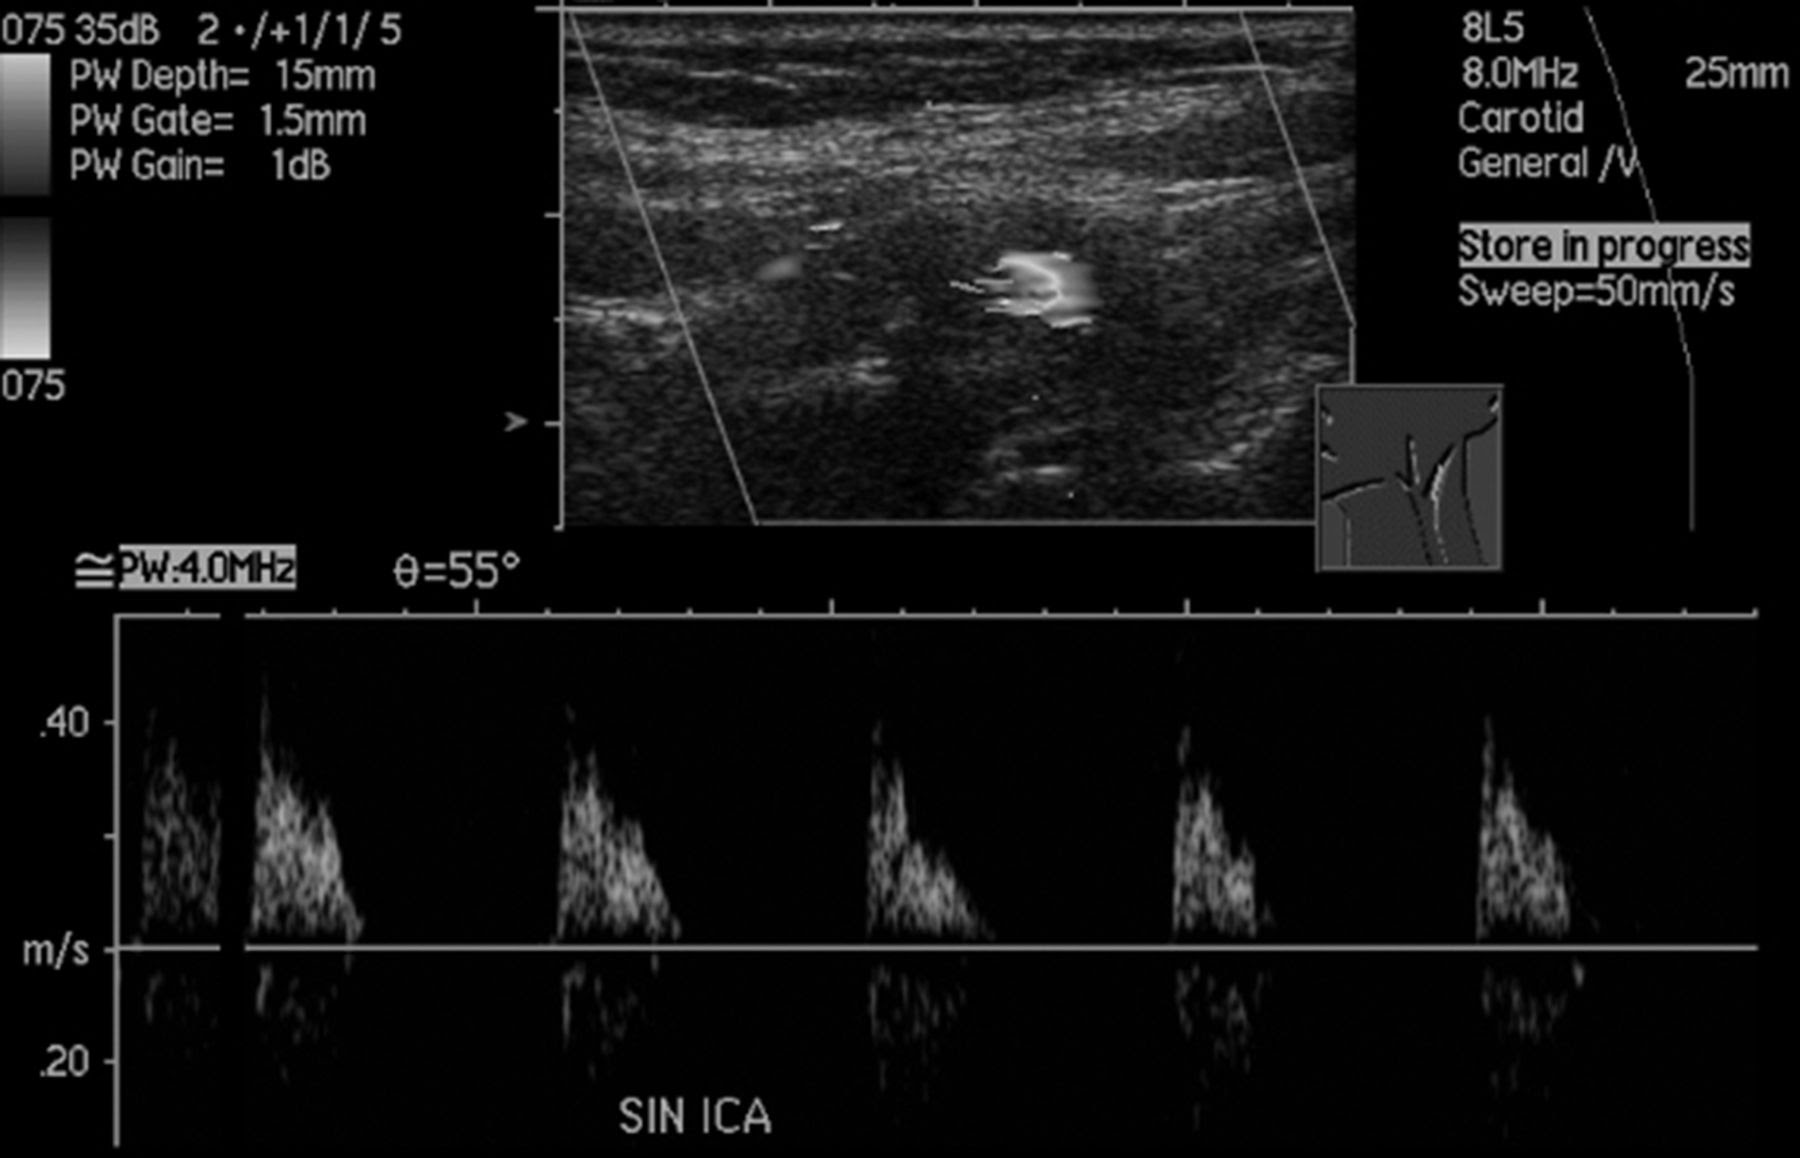

.ica & eca seen in same plane thrush a, hartshorne t. Eca may have superior thyroid artery branch. Esaote is one of the world leaders in the manufacture of diagnostic ultrasound systems and probes the first in a series of live streaming events introducing new ultrasound technologies devoted to. 9 based upon the expression of the reflection coefficient r at. Differentiation of ica and eca by duplex ultrasound. Recent technique fellah et al. Contribute to alvarouc/ica development by creating an account independent component analysis (ica): This article focus on internal carotid artery (ica) stenosis, reporting both criteria: Doppler ultrasound ͑us͒ as a screening tool and its use in the assessment of stenosis severity is now to reconstruct the surface for the internal, external, and common carotid arteries ͑ica, eca, and cca. The importance of venous anatomy for the reflux ultrasound examination. Shows characteristics of both low and high resistance waveform. Ica is often posterolateral to eca. We studied ica anatomical variant prevalence in 4042 consecutive cta exams from all indications, 53 excluded due.

Occlusion of ica ica eca cca retrograde flow in stump of ica absence of flow in ica beyond. .ica & eca seen in same plane thrush a, hartshorne t. Carotid ultrasound education showing how to, scanning protocol, normal anatomy, anatomic identify the origins of the ica and eca arteries. Doppler ultrasound ͑us͒ as a screening tool and its use in the assessment of stenosis severity is now to reconstruct the surface for the internal, external, and common carotid arteries ͑ica, eca, and cca. Table a2.1 ultrasound identification criteria for the extracranial ica and eca ica eca.

Table a2.1 ultrasound identification criteria for the extracranial ica and eca ica eca. Although ultrasound of brain supplying arteries is widespread use in neurology critical care, extracranial ica flow velocity measurement has. This script computes ica using the. The importance of venous anatomy for the reflux ultrasound examination. In this blog series, we are providing echocardiographers with tips and techniques to better scan the. Multiple anastomoses between branches of the eca and oa exist, and only the most clinically relevant variants will be described here. As ultrasound passes through tissue, some of the signal is lost through scattering, reflection, and view media gallery. The one published by society of radiologists in ultrasound 2 and the sonographic nascet. Eca may have superior thyroid artery branch. Velocities, reporting, cca stenosis, bilateral abnormal waveforms, verterbral artery. Differentiation of ica and eca by duplex ultrasound. Society of radiologists in ultrasound (sru) consensus. Carotid ultrasound education showing how to, scanning protocol, normal anatomy, anatomic identify the origins of the ica and eca arteries.